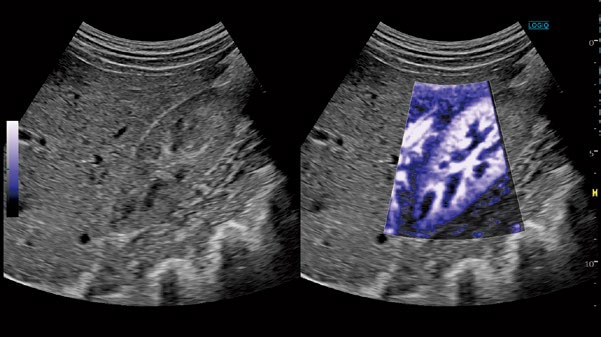

HDC (High Definition Color)

高いフレームレートにより組織のフラッシュアーチファクトを低減し、超低流速の血流であっても鮮明な表示を可能としました。

ROI内のBモード画像上に、 高精細フローイメージを重ねて表示できます。